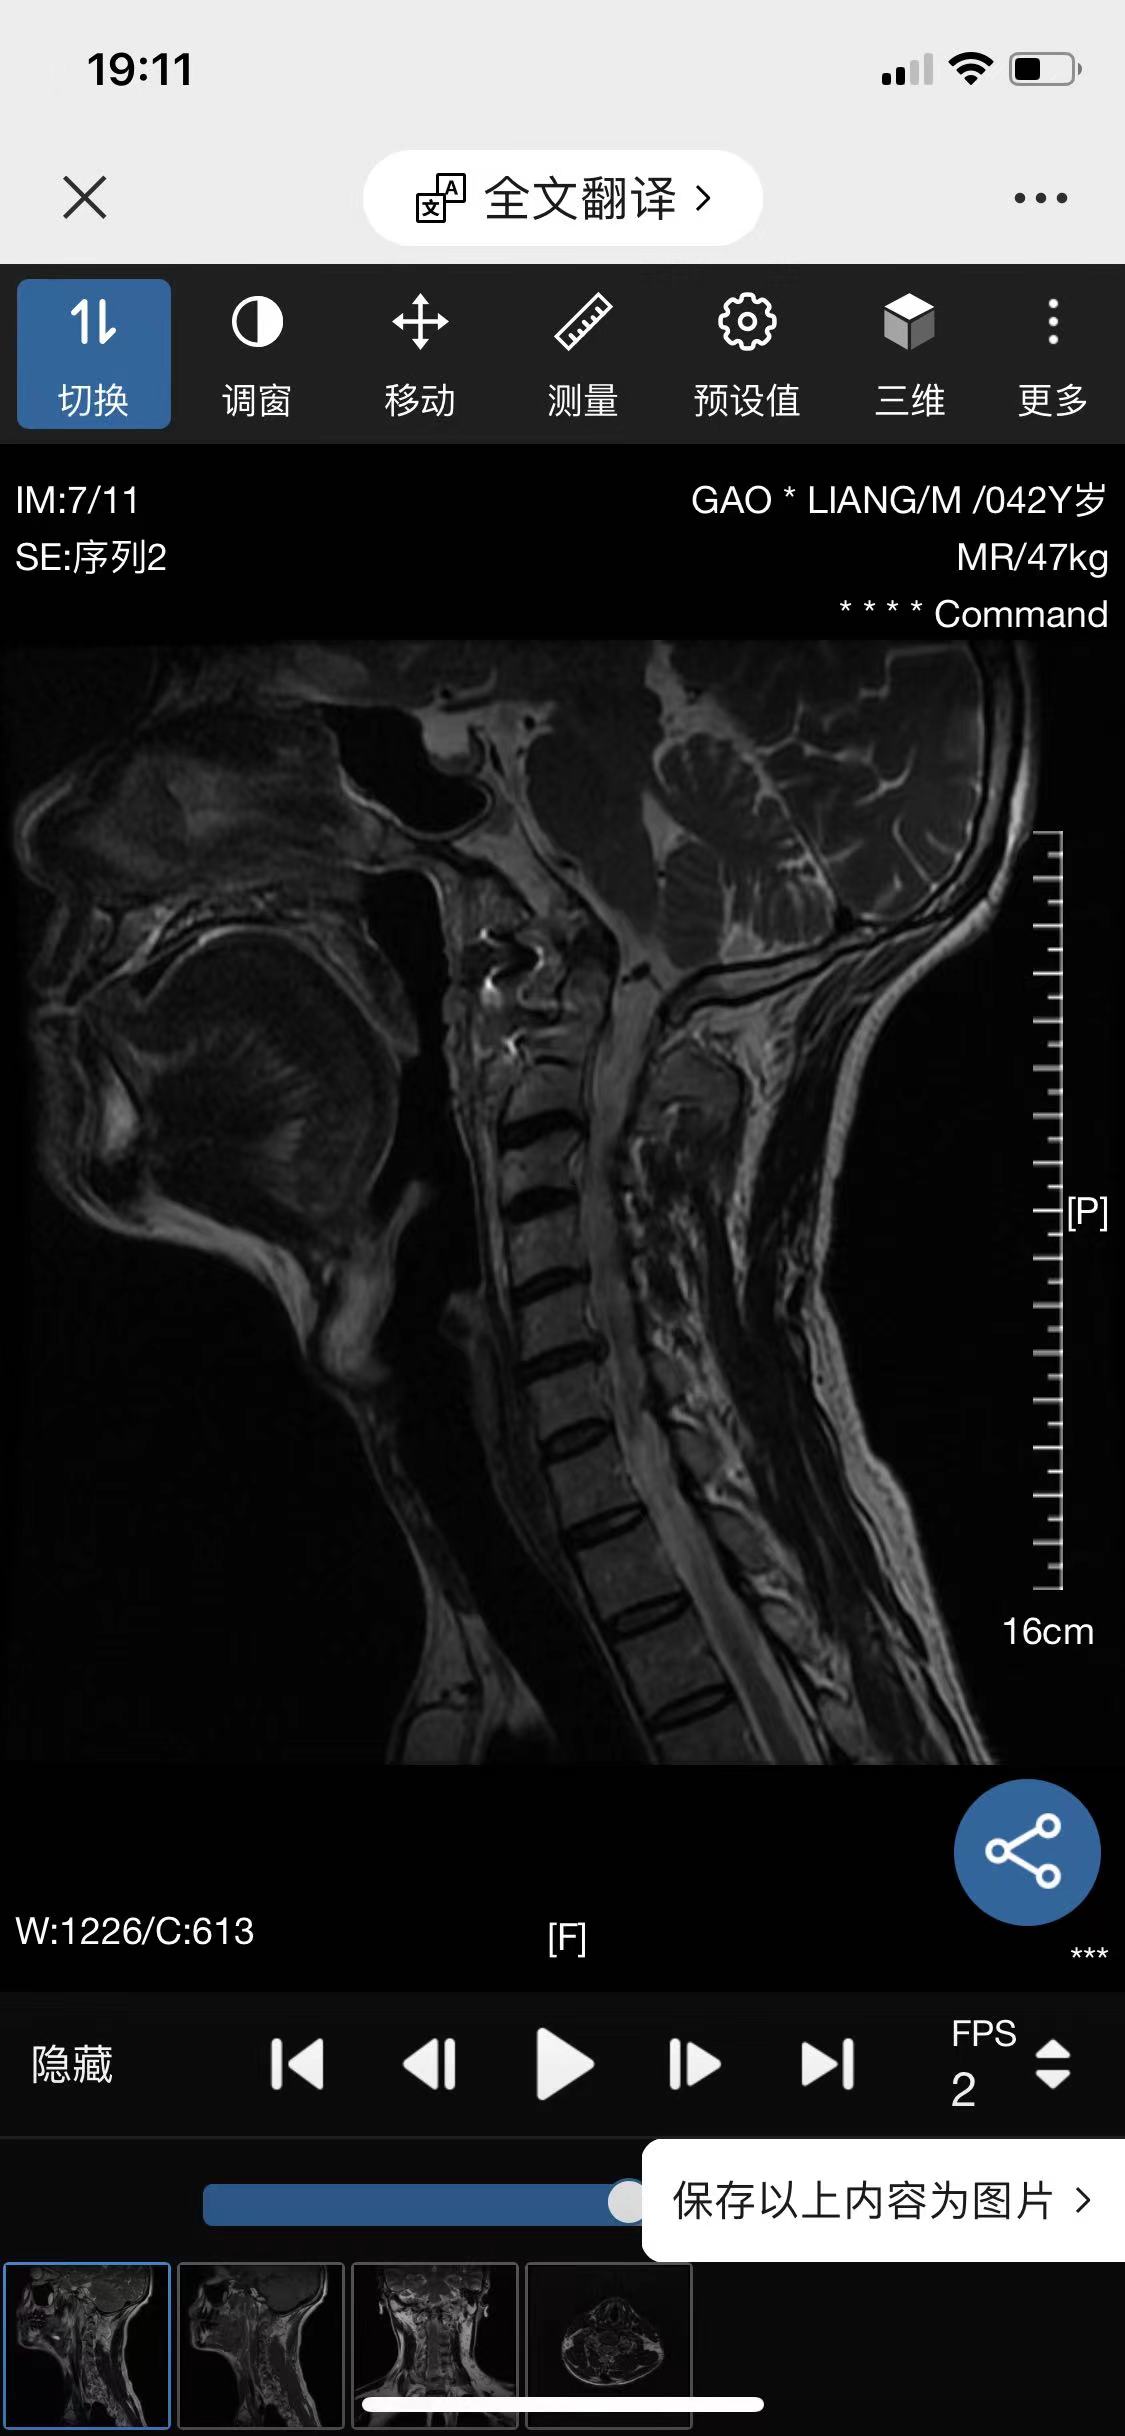

• 诊断:寰枢椎脱位

• 影像: